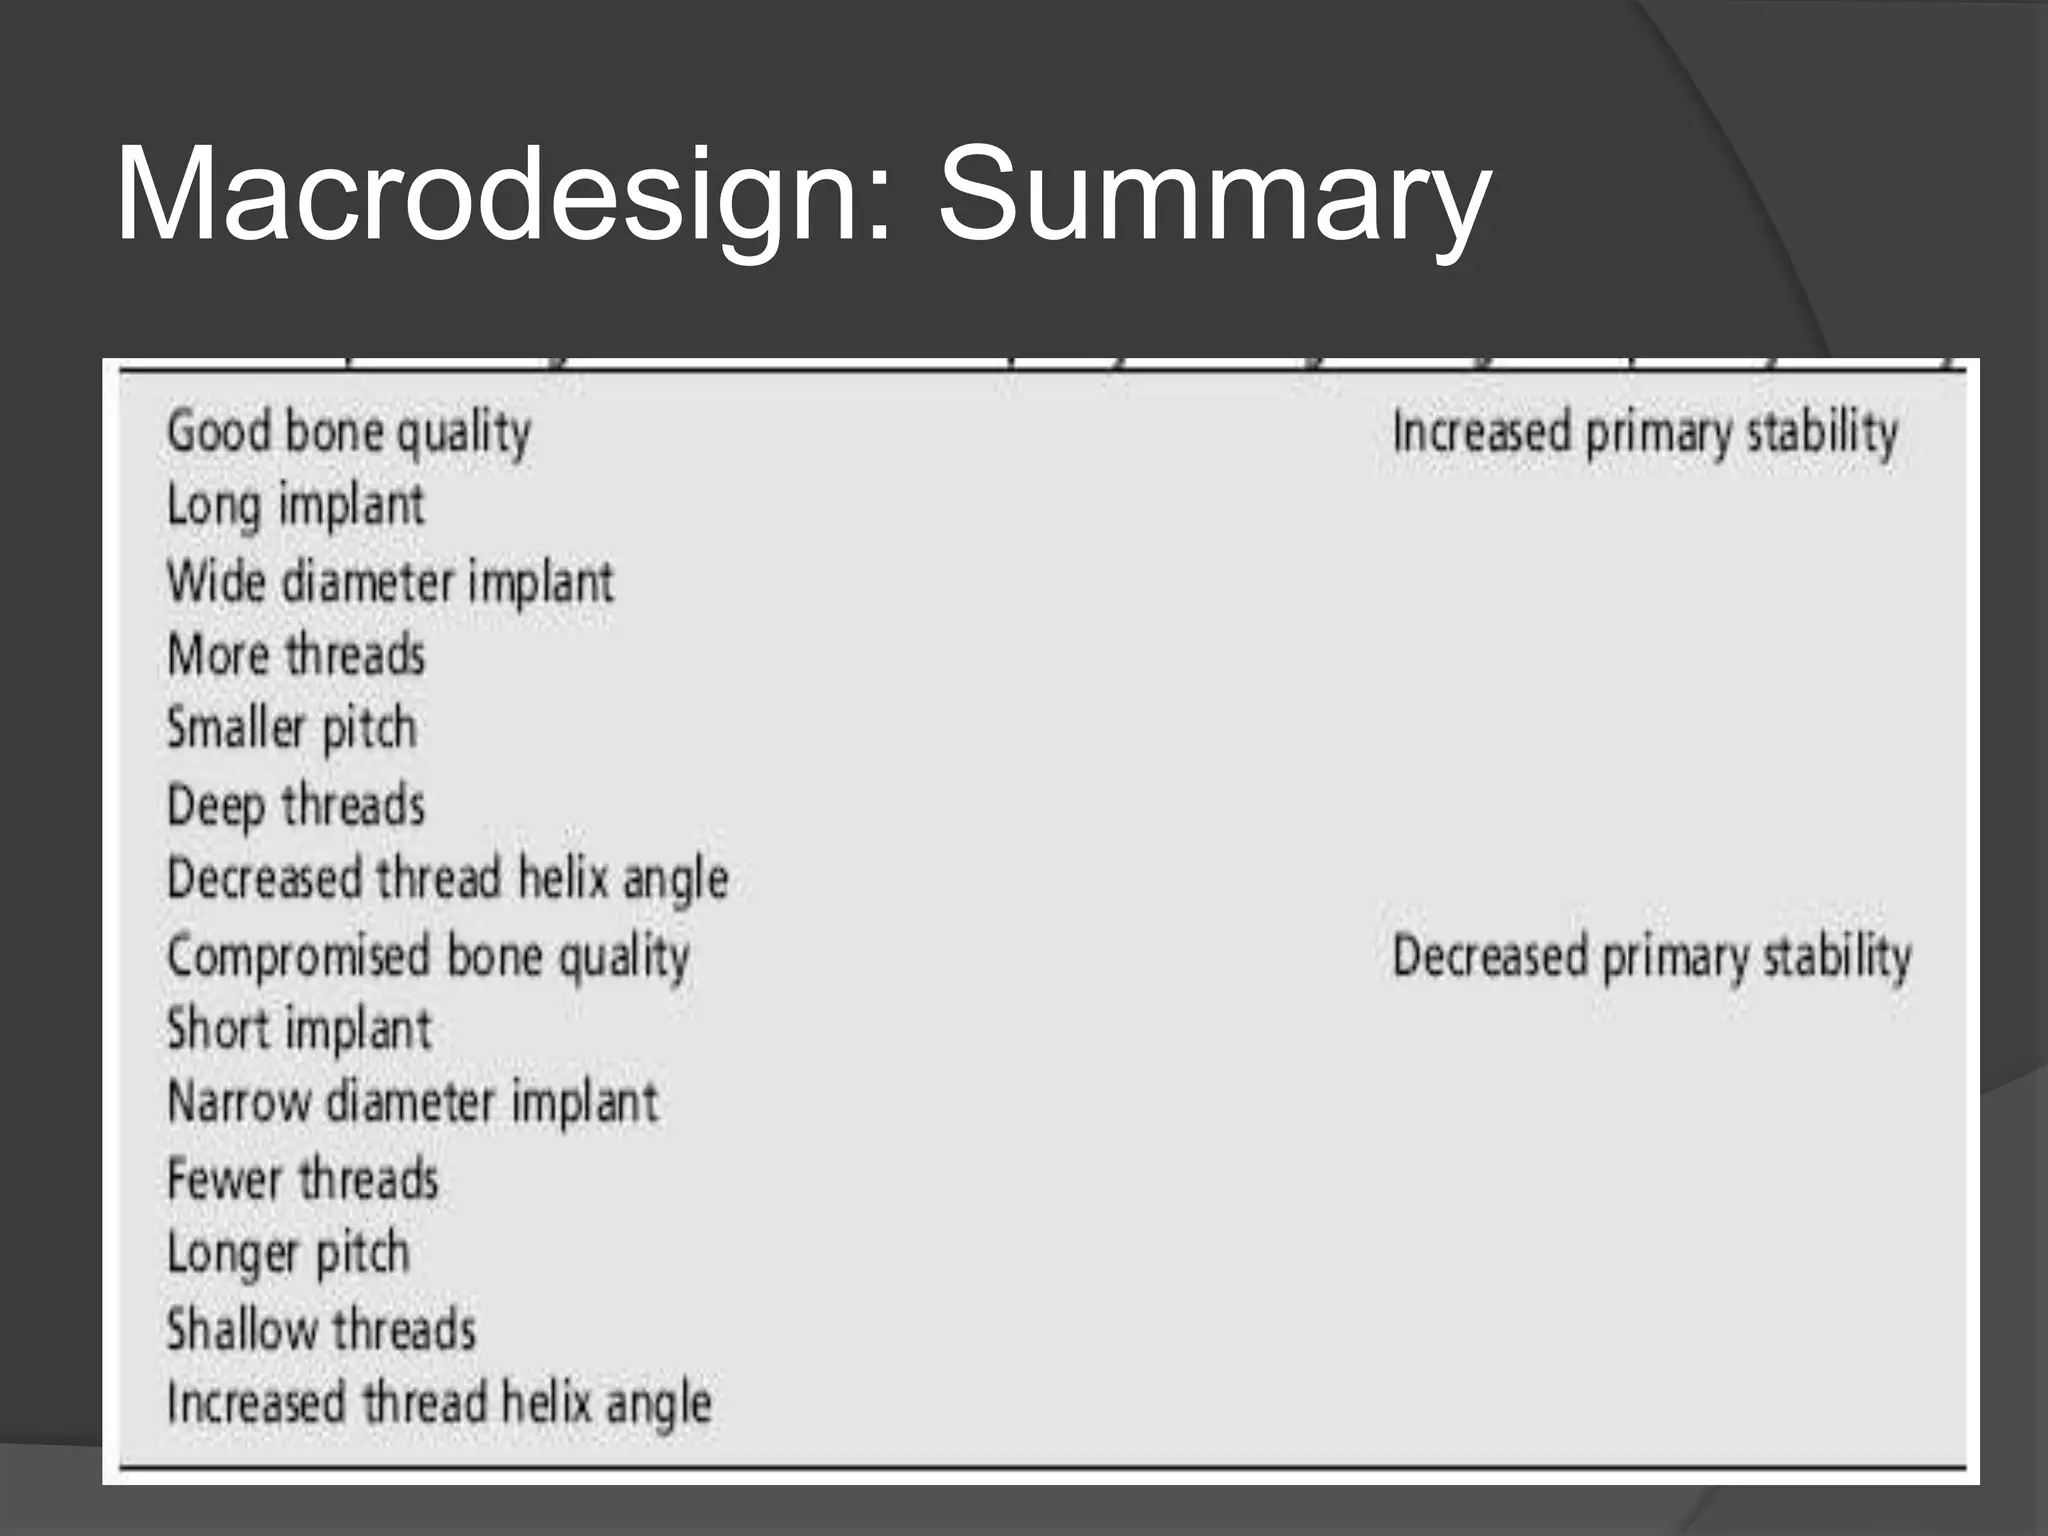

This document discusses factors that influence osseointegration and primary stability of dental implants, including implant design characteristics, surgical technique, and loading protocols. Specifically, it covers the processes of osseointegration and how forces on implants can either promote or inhibit bone remodeling. Key implant design considerations like length, diameter, threads, coatings and surface topography are analyzed in terms of their effects on stress distribution and bone-implant contact. The importance of primary stability and factors influencing it like bone quality and surgical skill are also addressed. Loading protocols ranging from immediate to conventional loading are compared.